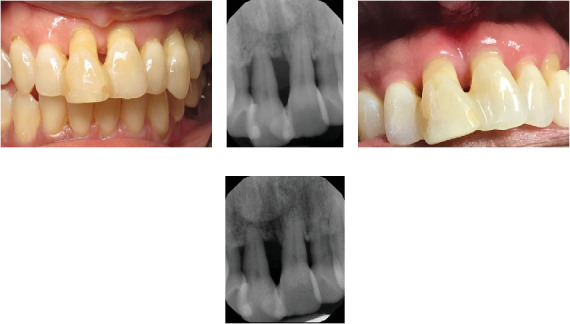

目的:牙周夹板为稳定活动牙提供了一种无创、廉价的治疗方法。本研究评估牙周夹板的使用寿命和长期稳定性。方法:对上颌前牙或下颌前牙接受夹板的患者进行回顾性分析。收集的数据包括患者的年龄、性别、夹板放置的指征、放置的日期、所涉及的牙齿、骨质流失的百分比、桥桥的存在以及加固的类型。数据用描述性统计进行汇总。采用t检验分析骨质流失的差异。结果:本研究共纳入154例。患者平均年龄为57.2岁,年龄范围从17岁到93岁,男性和女性的比例几乎相等(54%对46%)。手术从2003年进行到2024年。大多数是下颌夹板(20%)或没有桥架(47%)。上颌夹板占33%的样本(12%有桥式,21%没有)。68% (n = 105)的病例的夹板是牙周的。创伤占18%,包括口腔穿孔和撕脱。在有资料的情况下,评估牙周病例的骨质流失情况。平均损失为76.5%,从30%到100%不等。骨丢失与夹板的位置(p值= 0.3690)、患者性别(p值= 0.3391)或夹板加固的使用(p值= 0.3548)无显著相关性。只有40%的夹板得到了加固。超过一半的病例的寿命为10年或更长(n = 82,55%)。结论:夹板可为活动牙提供长期支持,有助于牙周受损牙的维持。在替换单个前牙时,带桥托的夹板可以提供稳定的临时假体作为临时可移动矫治器的替代方案。

Objective: Periodontal splints offer a noninvasive and inexpensive treatment modality to stabilize mobile teeth. This study evaluated periodontal splints to examine their longevity and long-term stability. Methods: A retrospective chart review was performed for patients who received splints on mandibular or maxillary anterior teeth. Data collected included patient age, gender, indication for splint placement, date of placement, teeth involved, percent bone loss, presence of a pontic, and type of reinforcement. Data were summarized with descriptive statistics. Differences in bone loss were analyzed using t-tests. Results: A total of 154 cases were included in the study. The average patient age was 57.2 and ranged from 17 to 93, with nearly equal rates of males and females (54% vs. 46%). Procedures were performed from 2003 until 2024. The majority were mandibular splints with (20%) or without a pontic (47%). Maxillary splints accounted for 33% of the sample (12% with pontic and 21% without). The nature of the splint was periodontal for 68% (n = 105) of the cases. Trauma accounted for 18% and included incidents with oral piercings and avulsion. Periodontal cases were assessed for bone loss where data were available. The average loss was 76.5% and ranged from 30%to 100%. Bone loss was not significantly associated with the location of the splint (p-value = 0.3690), patient gender (p-value = 0.3391), or use of splint reinforcement (p-value = 0.3548). Only 40% of splints were reinforced. More than half of the cases had a longevity of 10 or more years (n = 82, 55%). Conclusion: Splinting can provide long-term support to mobile teeth and aid in maintaining periodontally compromised teeth. In replacing single anterior teeth, a splint with a pontic can provide a stable provisional prosthesis as an alternative to a temporary removable appliance.